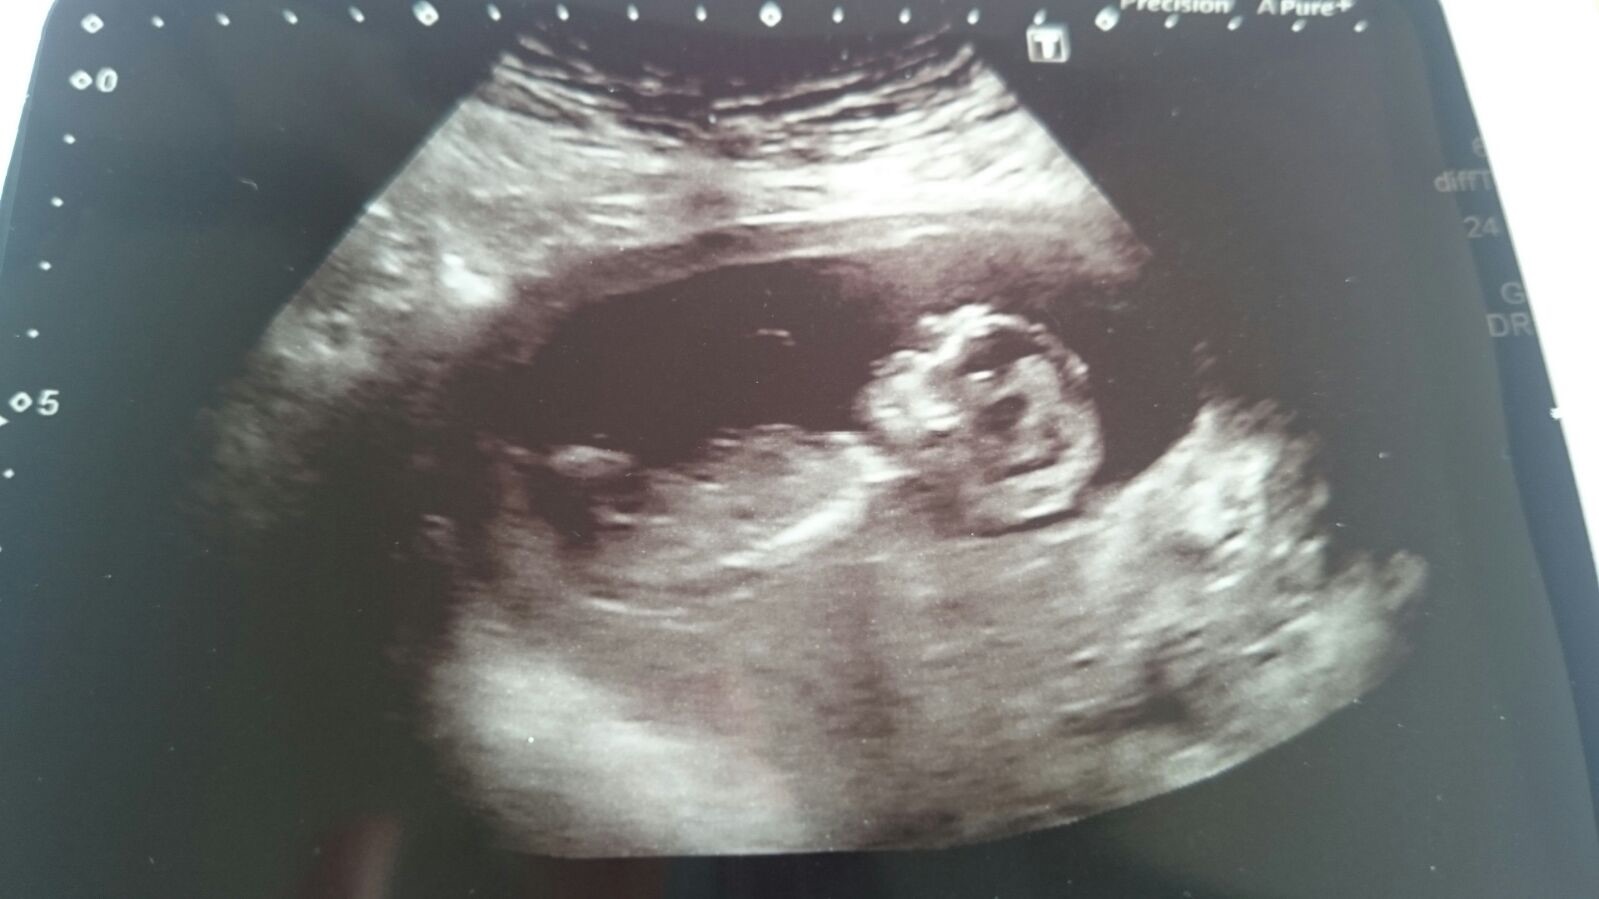

Any guesses on this scan pic of 13weeks and 3 days?? I'm pretty sure that is the nub and a good pic too so hopefully I'll get a fair idea of pink or blue :-)Attachment 27359

It's a bit hard to see because its not that close up but maybe girl?

I think that looks like a pretty good nub pic! That is... If that is indeed the nub. Lol. I'm no expert, but I would say girl.

I guess boy but it's not really clear

Leaning girl

Girl lean but yes, not very clear.